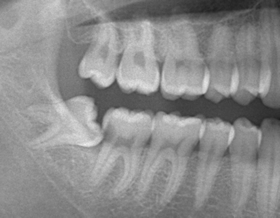

下あごの親知らず

当院においては開業医では避けられてしまう下あごの親知らずの抜歯を積極的に行っていきます。

下の親知らずに関しては、必ずしも抜歯しなくてはいけないということはありません。

抜かなければならない場合もあれば、触らない方が良い場合もあります。

他院で「下あごの親知らずがあるから抜歯をするように」と大学病院を紹介された患者様も当院にいらしていただければ、ご相談に乗らせていただきますし、必要があれば当院で抜歯を行います。